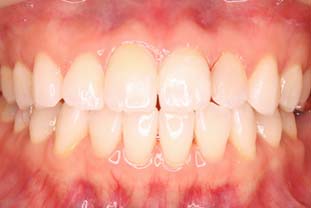

デュアルホワイトニング

+オールセラミックの症例

| 年齢・性別 | 29歳・女性 |

| 治療期間 | 3ヶ月 |

| 治療内容 | デュアルホワイトニング +オールセラミック |

| 治療本数 | 12本 |

| 治療費用 | デュアルホワイトニング(77,000円(税込)) +オールセラミック(165,000円(税込)×12本) |

| 副作用等 | ホワイトニングの効果には、個人差があります。 術後、知覚過敏が生じることがありますが、 ほとんどの場合1〜2日で治まります。 噛む力が強い方の場合、セラミックが欠けて しまうことがあるので、就寝時にマウスピースを 装着していただく必要があります。 |